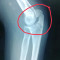

Selamat sore dokter, terkhusus dokter Spesialis Orthopedi

Mohon advisnya dokter

Jadi ada pasien mengeluhkan nyeri seperti tertusuk, tidak selalu, tapi sering, hilang timbul

Pasien post Orif ps H+113/6 bulan (tanggal 06 Agustus 2024)